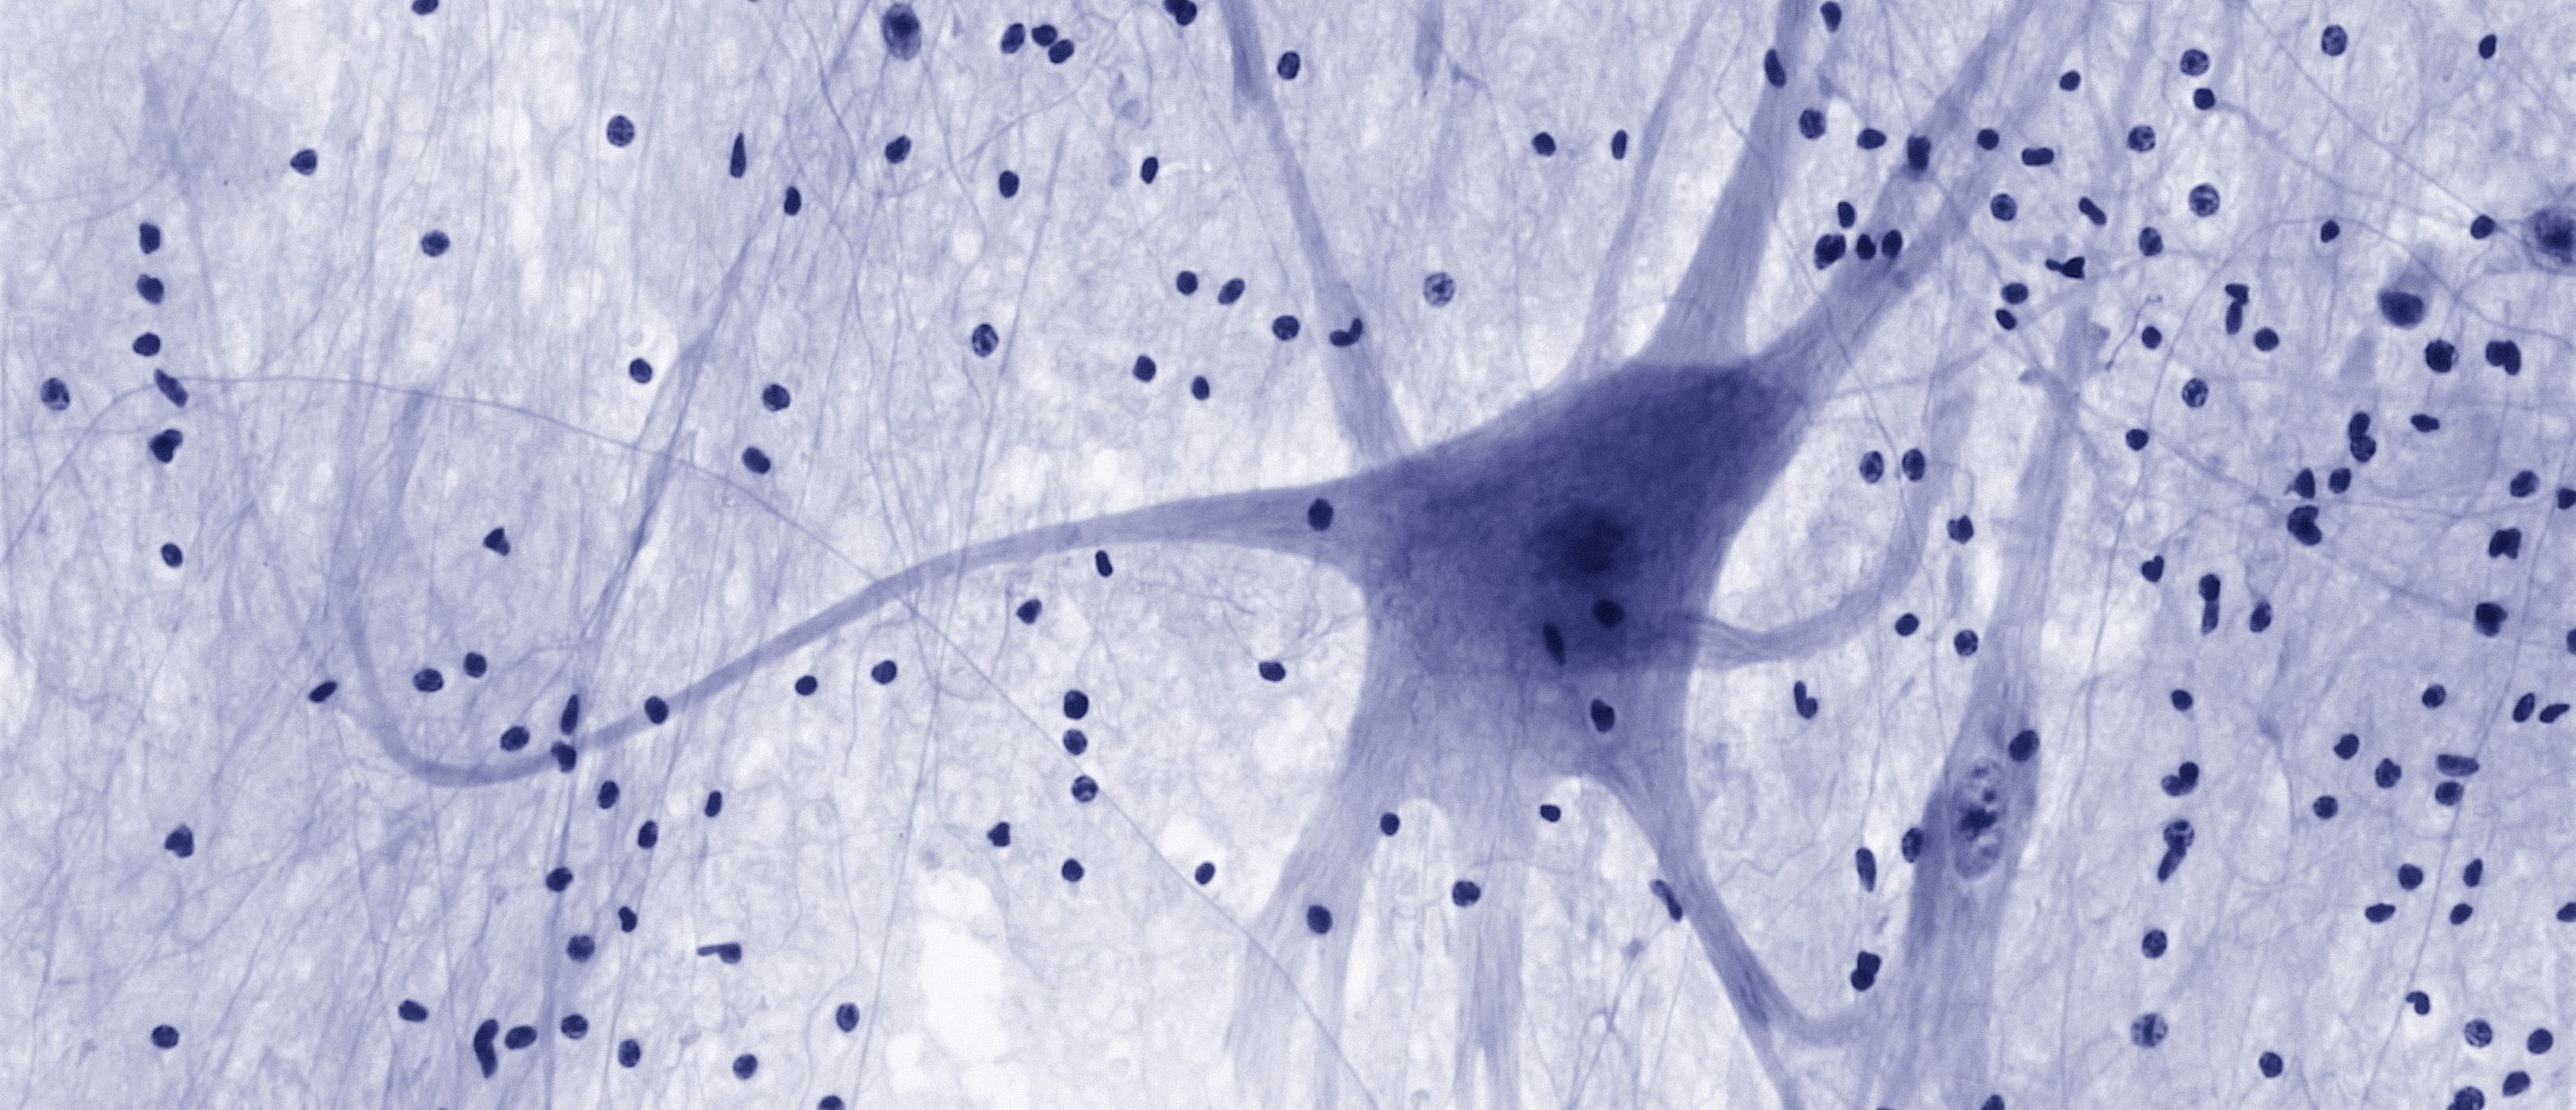

Our guests visited laboratories such the Hamlyn Centre – at the forefront of research into medical imaging, sensing and robotics – and the Centre for Bio-inspired Design, which takes its inspiration from the natural world to drive healthcare innovation. They also got the chance to meet an array of entrepreneurs whose research began at Imperial, and whose companies are now developing cutting-edge innovations in cancer treatment, neural implants, gene therapy, and disease monitoring.